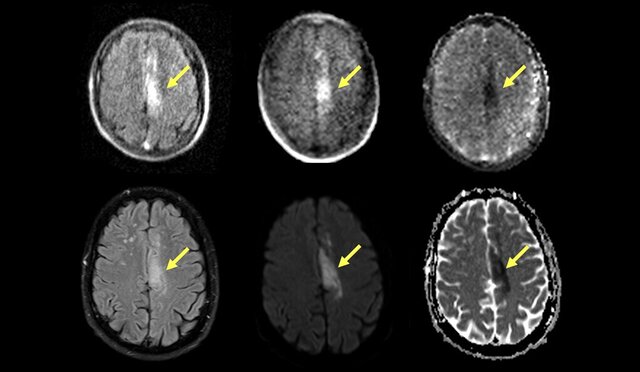

ابتدا از هر بیمار توسط دستگاه MRI معمولی برای تایید تشخیص سکته مغزی ایسکمیک تصویربرداری شد. سپس هر بیمار با دستگاه MRI جدید قابل حمل، اسکن شد و این دستگاه جدید توانست لختههای خون در مغز را با دقت ۹۰ درصد تشخیص دهد.

این دستگاه قابل حمل در انواع بخشهای اورژانس و مراقبتهای ویژه آزمایش شد و مشخص شد که لختههای خونی به کوچکی ۴ میلیمتر را تشخیص میدهد.